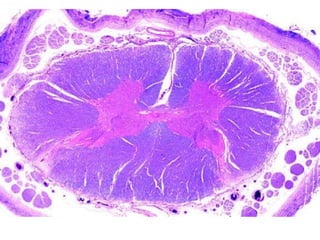

FIBRAS NERVIOSAS.Son estructuras largas y delgadas, especializadas en la conducción de los impulsos nerviosos.Están constituidas por un axón y sus vainas envolventes.

FIBRAS NERVIOSAS.Son estructuraslargas y delgadas, especializadas en la conducción de los impulsos nerviosos.Están constituidas por un axón y sus vainas envolventes.